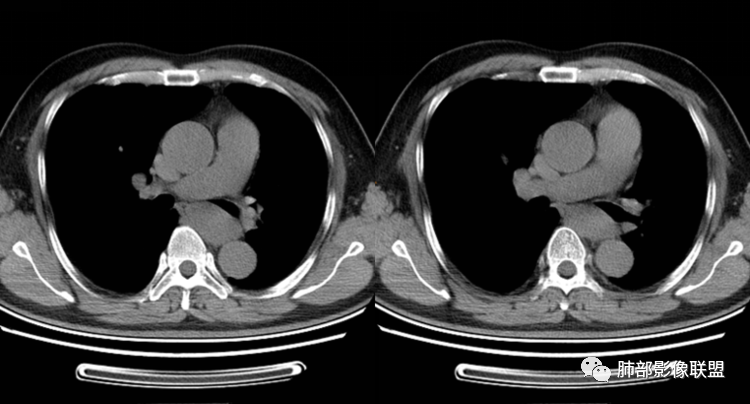

患者,男,43岁,无意间发现纵隔肿物,无胸闷胸痛,无心慌气短,无咳嗽,无吞咽困难等不适。体检发现的,无症状。

气管、左主支气管后方,食道左侧囊性占位,壁薄且均匀、光滑。气管及左主支气管受压凹陷、变形。

食道也受压变形、移位。

支气管囊肿

影像学表现

(1)圆形或椭圆形、边缘光滑的病灶,囊壁薄,囊壁可见钙化;由于病变的支气管起源性,囊壁可见属于气管壁的软骨成份.

(2)囊液密度均匀,根据性质的不同而呈不同密度,可为近似水样密度,也可为较高密度,因为囊壁分泌粘液,所以囊内密度一般高于其他纵隔囊肿,CT值多大于20HU甚至超过60HU;

(3)若囊肿内密度较高时与实性肿块鉴别较为困难,增强扫描囊液无强化为鉴别要点;但是囊壁因为含有平滑肌成份,所以可能环形强化;如果病灶合并感染,病灶壁也会明显强化。